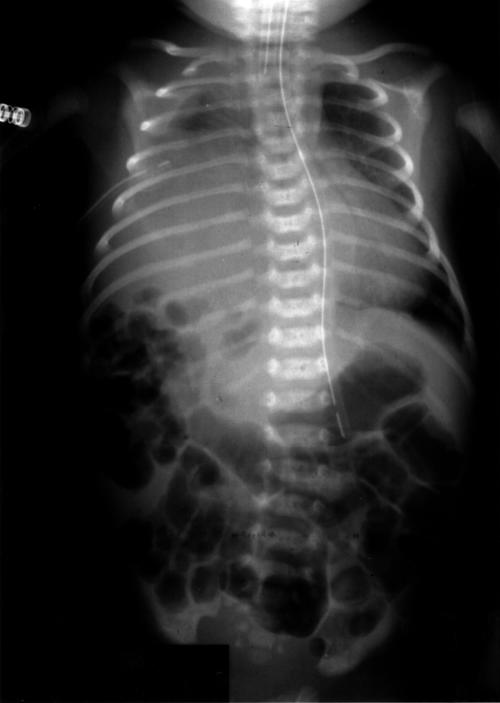

Figure 2.

Chest radiograph following insertion of chest drain, showing partial drainage of the pleural effusion. The liver shadow and bowel gas are now seen in the right hemithorax